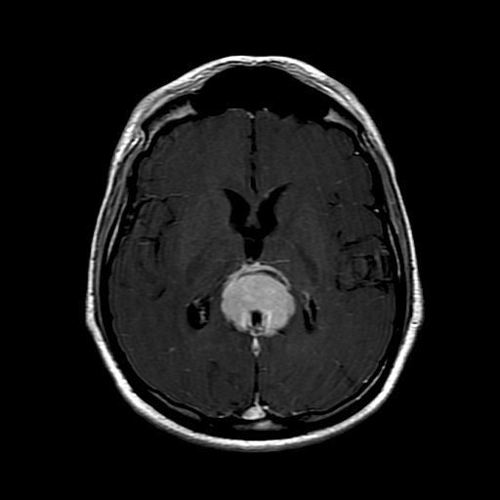

Imaging of the Case: MRI demonstrated a 4.4 x 3.5 x 4.7 cm mass in the pineal region. The lesion is isointense on T1 with homogeneous post contrast enhancement (Panel A) and slightly hyperintense on T2. The tumor is relatively well demarcated. The tectal plate is not visualized and mass effect is demonstrated upon the third ventricle outflow tract and midbrain. A second but smaller lesion of similar imaging characteristic is dmonstrated in the suprasellar region involving the optic chiasma. There is also mild hydrocephalus. CT scan (Panel B) demonstrated also a similar enhancing lesion. Calcifications are demonstrated on both MRI and CT scan.